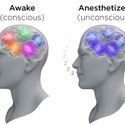

Revealing the Brain through States of Unconsciousness

11/15/11 Important insights into the brain from research on anesthesia, coma and sleep. Emery N. Brown